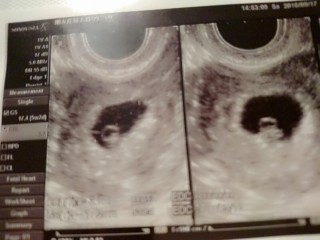

初診では胎嚢、卵黄嚢確認、周期は多分5wくらいとはっきりせず。 そして二回目の健診で赤ちゃんの心拍確認出来ました!!!胎芽3.7㎜!胎嚢13.5㎜!もう嬉しくて嬉しくて笑泣き!順調ですねと先生から言われてニヤニヤが止まらず!大きさ、心拍確認で6wと決定しました。左の卵巣が腫れてるけど排卵?したせいなのでこれは問題無いですと言われて安心です。 一年ほど前に稽留流産を経験しました。あんな辛い思いはもうしたくありません。まだまだ不安だらけですが皆さん頑張りましょう!赤ちゃんを信じましょう!リラックスしてそして強い意志で赤ちゃんと頑張りましょうね!!!